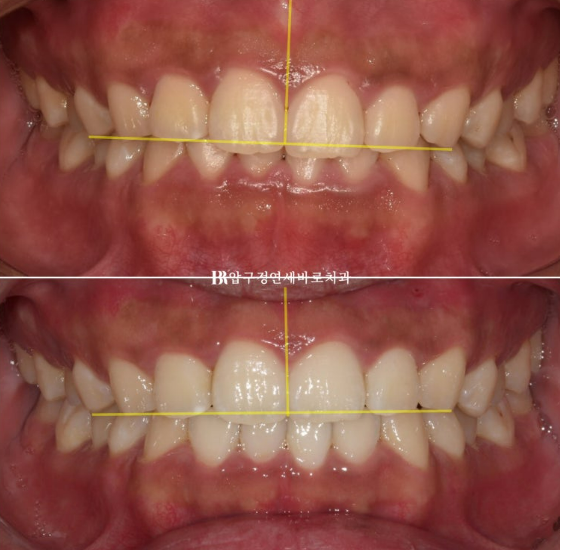

24.02-24.07

As the deep bite was relieved, the lower teeth are now visible when biting down.

24.02~24.07

These are the changes over 4 months with Invisalign Lite.

The patient’s excellent cooperation, the use of orthodontic mini-screws,

and an appropriate treatment plan created good results in a short period.

If you draw a reference line, the improvement in the occlusal plane tilt becomes even easier to see.